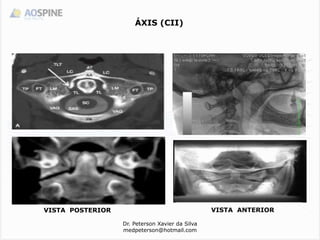

ÁXIS (CII)

VISTA ANTERIOR

VISTA POSTERIOR

 o dente constitui um pivô no qual o atlas e a cabeça fazem

rotação.